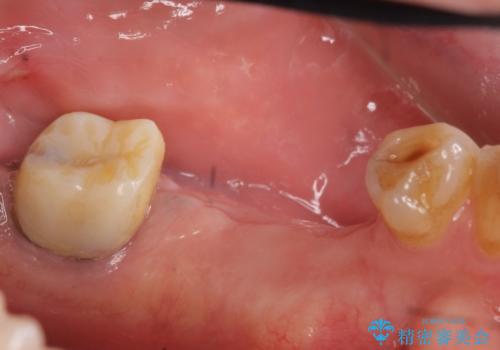

- 左下奥歯が虫歯で抜歯になってしまったため、インプラントにしたいといらっしゃった方の症例です。

欠損部位である左下5、6番目にインプラントを埋入し、オールセラミッククラウンによる補綴を行いました。

左下7番目は再根管治療を行い、オールセラミッククラウンによる補綴を行いました。